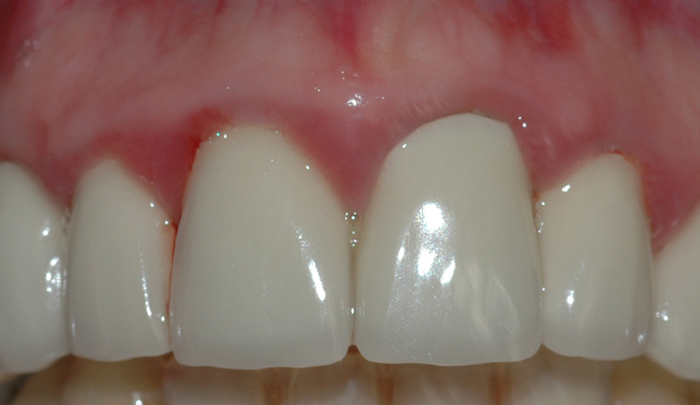

Et friskt tannkjøtt har lys rød farge og ligger stramt inntil tennene (fig. I). Et betent tannkjøtt får en mørkere rødfarge, det blir hovent og kan føles ømt ved berøring. Videre vil man kunne oppleve at tannkjøttet blør ved rengjøring og at det ligger mindre stramt inntil tennene.

Fig 1: Et friskt tannkjøtt har lys rød farge og ligger stramt inntil tennene Fig 2: Mangelfullt renhold kan over tid føre til utvikling av gingivitt